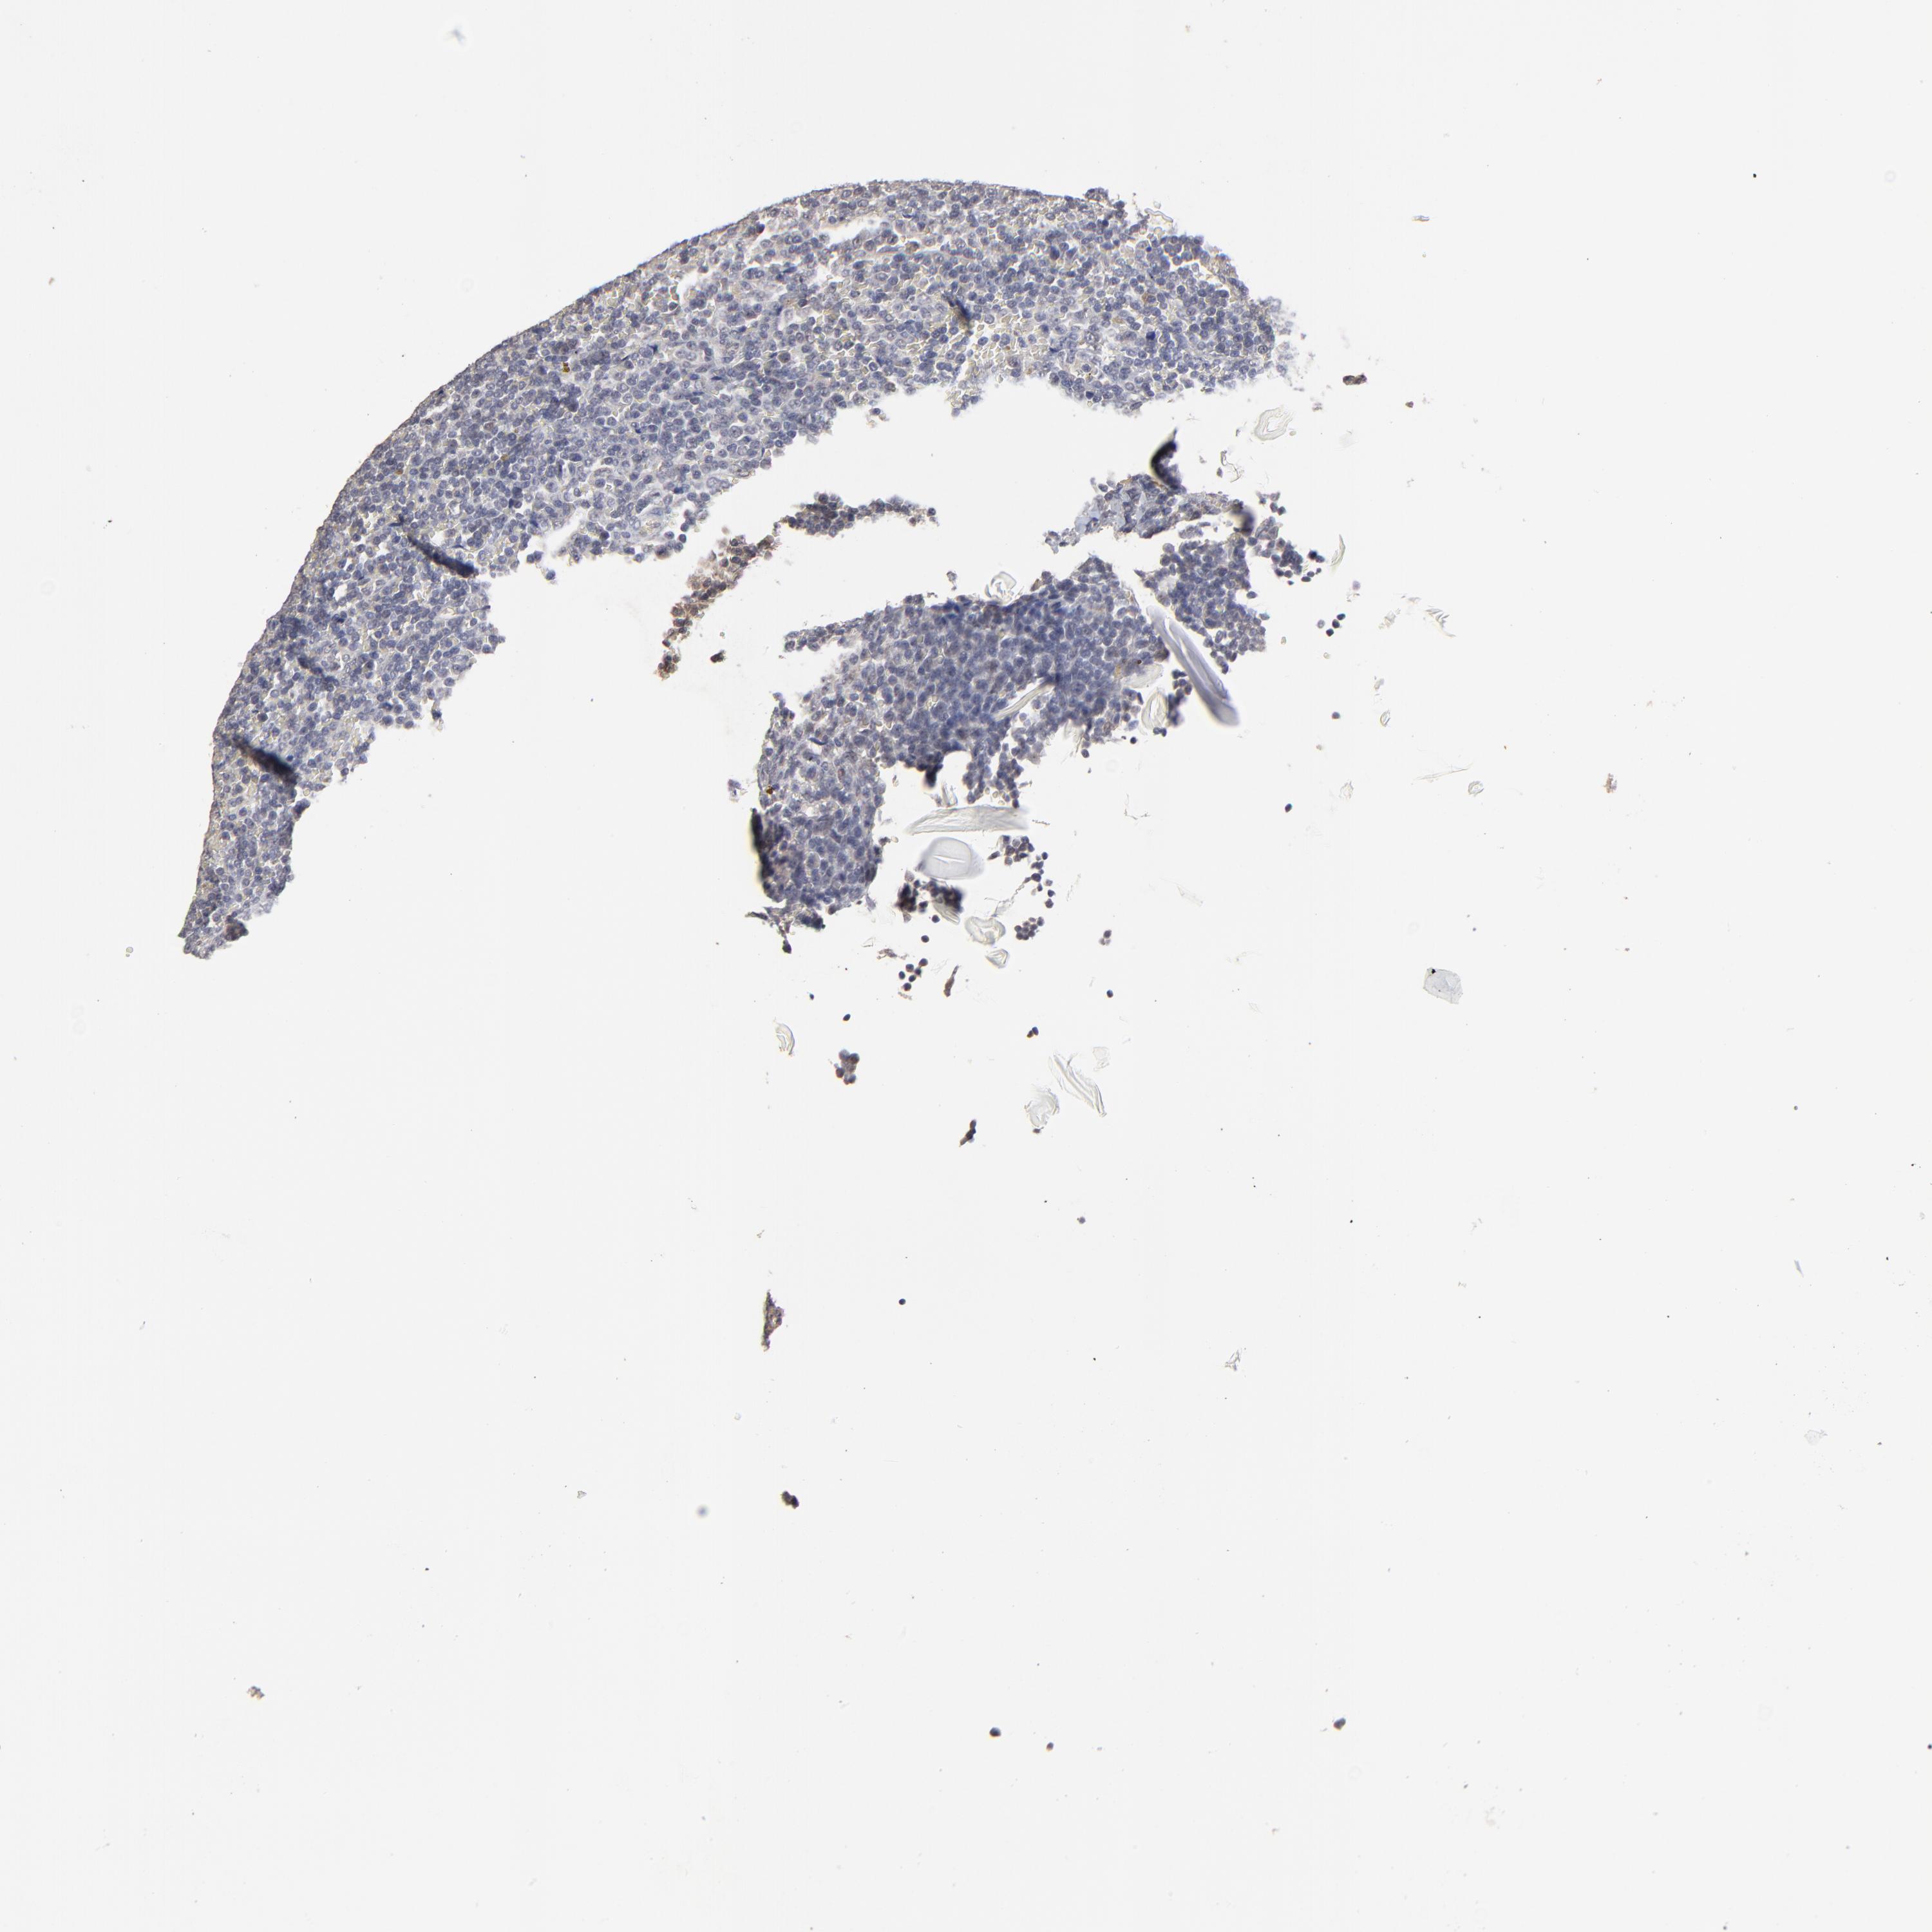

Antibody HPA003093

Staining

High

Medium

Low

Not detected

Intensity

Strong

Moderate

Weak

Negative

Quantity

>75%

75%-25%

<25%

None

Location

Nuclear

Cytoplasmic/membranous

Cytoplasmic/membranous,nuclear

Malignant lymphoma, non-Hodgkin's type, High grade

Hodgkin's disease, NOS

Malignant lymphoma, non-Hodgkin's type, Low grade